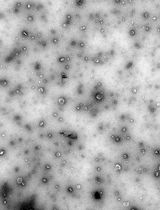

Every year, there is an increase in the number of cases of chronic kidney disease, and a delay in the initiation of adequate treatment can lead to kidney failure, which requires regular dialysis or transplantation. Intensive systemic therapy used to treat kidney diseases often has a negative impact on other weakened organs, making it crucial to ensure targeted delivery of medications directly to the kidneys and to minimize systemic side effects. In order to reduce the toxicity of medications and decrease dosages, innovative delivery methods are being developed, such as micro-sized targeted delivery systems, which ensure highly effective distribution of encapsulated drugs directly within the organs. In a recent article, we presented innovative emulsified microgels stabilized with whey protein isolate (WPI), specifically designed for targeted drug delivery to the kidneys. Our stability studies revealed that these microgels start to degrade after 72 h, with this degradation exhibiting a time-dependent profile. Furthermore, intravenous administration of the microgel suspension through the tail vein showed significant selective accumulation in both the liver and kidneys over a duration of 5 days. As part of our research, we present the protocol for synthesizing emulsion microgels derived from whey protein isolate. This article provides a comprehensive overview of the procedures for precursor preparation, along with an in-depth investigation of the emulsion system's stability over time. The protocol also includes the injection of an emulsion microgel suspension into the tail vein of mice, enabling the evaluation of their biocompatibility and potential therapeutic efficacy. This protocol outlines the precautions and important nuances that should be considered at each stage of the experiment.

Modification of emulsions with mucoadhesive components allows an increase in targeting of the drug delivery system, their retention on the mucous surface of organs, and, at the same time, the localization, safety, and effectiveness of the administered drug. The use of mucoadhesive emulsions is gaining popularity due to their unique combination of properties that make them ideal for delivering drugs directly to the mucosal surfaces. In our study, we use the naturally derived mucoadhesive component whey protein isolate (WPI). WPI, along with its efficient mucosal specificity, provides the formation of the hydrogel shell at the oil surfaces upon the ultrasonically stimulated denaturation. In this way, the emulsion microgel system is formed.

Recently, we described the protocol for synthesizing emulsion microgels with high mucosal adhesion properties to the urothelium of the bladder provided by the mucoadhesive component, WPI [8]. We provided precautions and nuances that should be paid attention to at each stage of the experiment. During the study, the main physico-chemical parameters of microgels, such as filling capacity and drug release rate, were studied. The processes of drug release, both from the oil core of microgels (hydrophobic drug) and from the hydrogel protein shell (hydrophilic drug), strongly depend on the ionic strength of the medium in which microgels are incubated [8–10]. It has been shown that the ionic strength affects the degradation rate of protein hydrogel shells and, thus, the overall stability of microgels. This, in turn, affects the drug release behavior. The high ionic strength of the medium causes the high hydrophobicity of the protein molecules in the shell, which, accordingly, increases the stability of the microgels. The stability of microgels in artificial urine (0.3 M) is higher than in saline solution (0.15 M). Correspondingly, in artificial urine, the drug release from microgels demonstrates a more prolonged behavior, as compared with saline 0.15 M NaCl. The amount of hydrophilic drug released from the protein shell reaches 45% at 72 h of incubation in artificial urine [8]. The biodistribution of emulsion microgels in vivo after intravesical administration showed that local delivery ensures effective accumulation of carriers in the bladder due to the high adhesive properties of the protein on the surface of the microgels.

Due to the possibility of varying the synthesis conditions to produce microgels with precisely specified physical and chemical properties, such as particle size, surface area, zeta potential, and drug loading efficiency, emulsion microgels have been studied as a potential drug delivery system for the kidneys [11]. Intravenous delivery of these microgels resulted in a long-term accumulation (at least 5 days) of these particles in the liver and kidneys, indicating a high efficiency of biodistribution and targeting to the target organ. The experimental conditions for synthesizing these microgels allow for the creation of particles with exactly the desired characteristics. The developed microgels provide a customized therapeutic approach to the treatment of kidney diseases, with reduced side effects. This opens up new possibilities for the systemic treatment of the urinary system.